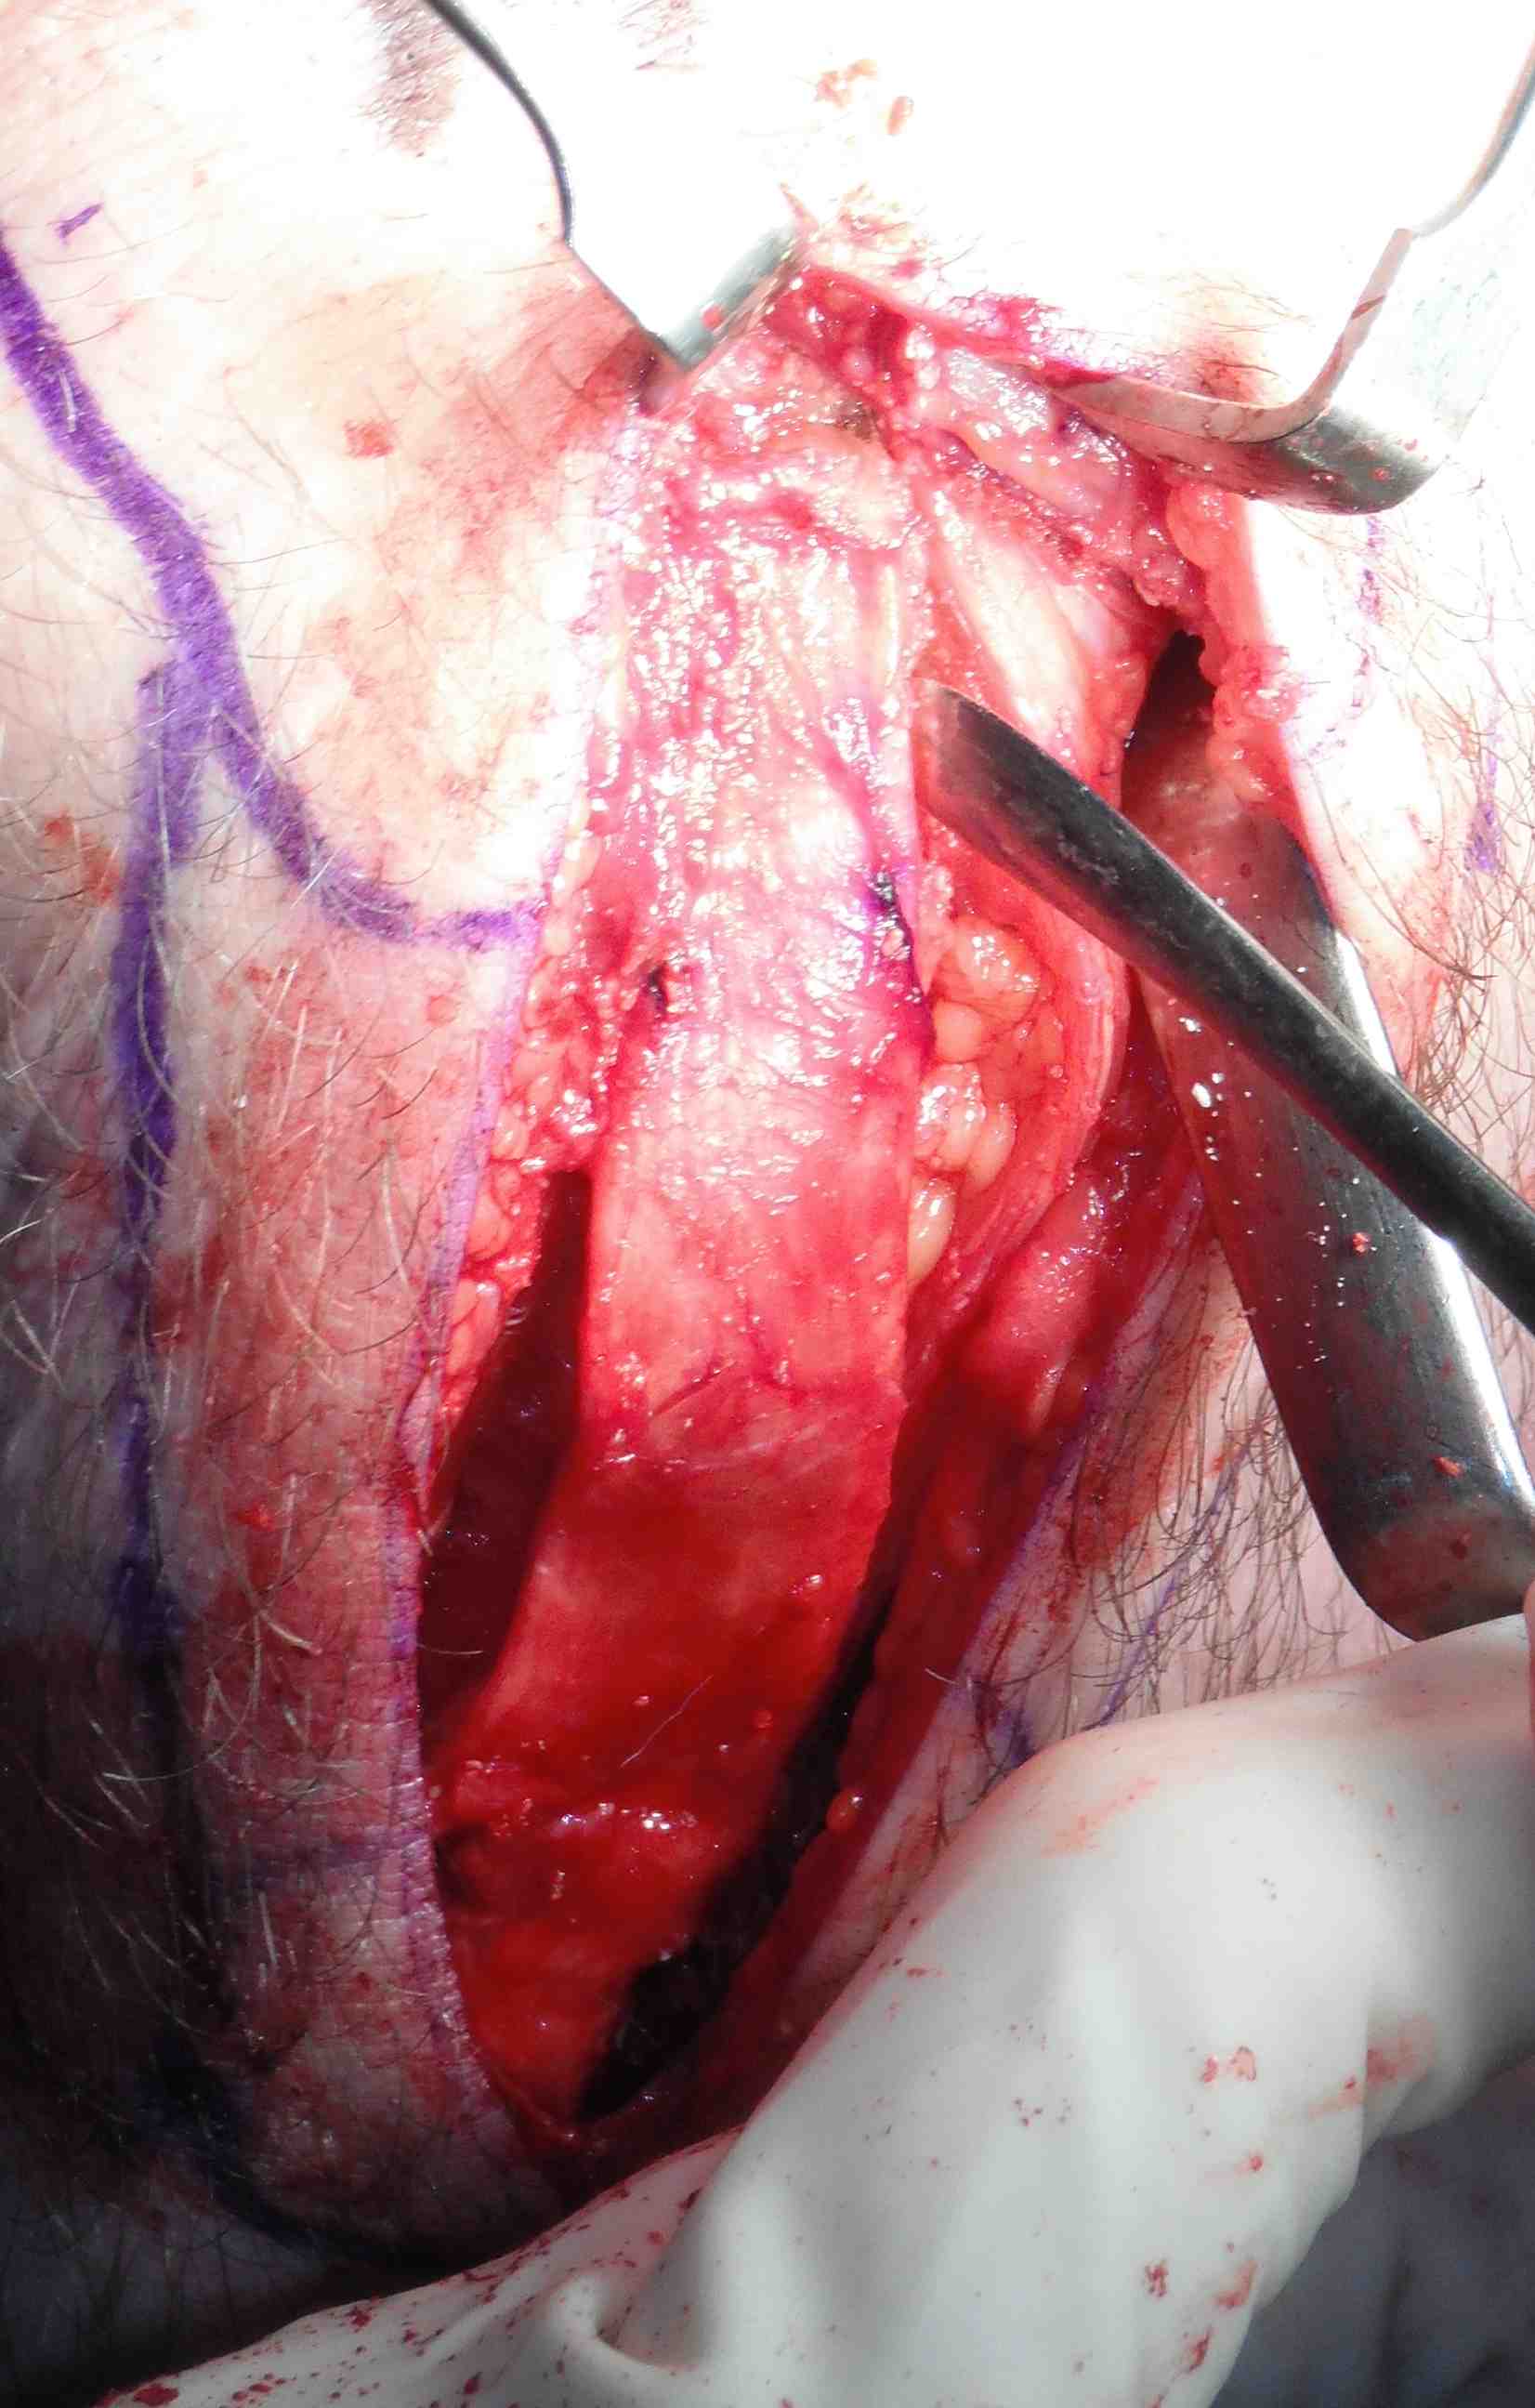

Bone blocks

- measure 2 x 1 cm bone block on tibial tuberosity

- cut each side at 45o with saw

- 1cm deep with each saw cut meeting as triangle

- distal transverse cut 1cm deep

- lever out with curved ostetome

- make 2 x 1.5 cm drill holes with piece in situ, mark with pen

Repeat on patella side, can push patella down for exposure

- use smaller lever on patella side and be more delicate

- remove graft carefully, have to dissect off the fat pad